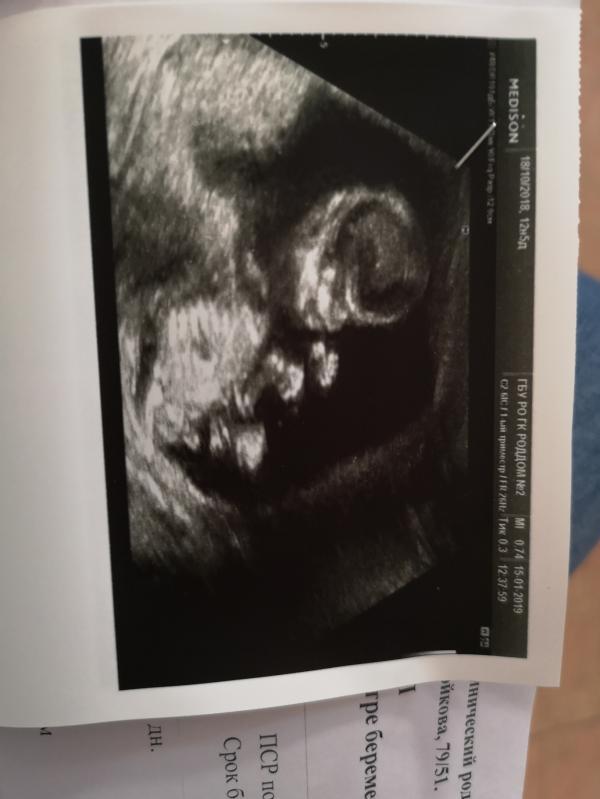

Сегодня узнали, что будет мальчик) имена готовила для девочки 😀 #14недель

30 мин осмотра Анной Юрьевной, не то что в нашей жк- 5 мин и готово. Поэтому для своего успокоения решила сходить в платный мед центр. Мне сказали, что отклоненмй нет, активист махал ручками все время, мешал рассмотреть сердечко, через 3 недели контроль узи.

Это вам на 14 неделе уже сказали пол? Это ж какая врач у вас хорошая. Сегодня была на скрининге. 12 недель и 5 дней. Сказала, что для пола ещё очень рано. Только в 19 скажут. А многим девчонкам в 12 предположительно говорят. Это что, от врача зависит? От квалификации?